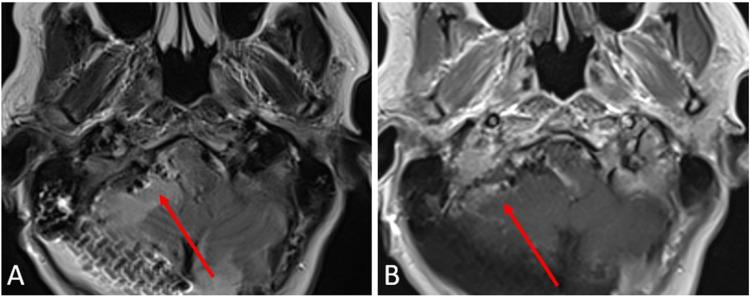

Calcifying pseudoneoplasm of the neuraxis are rare fibro-osseous lesions that can occur throughout the central nervous system. This paper reports one case of this lesion within the posterior fossa and contains a literature review of all cases documented within the posterior fossa to date. A 53-year-old female patient with a history of epiphora, facial irritation, and headaches was found to have a mass centered in the posterior fossa. The patient underwent surgical resection for removal of the mass. Upon review by pathology, the final diagnosis was consistent with calcifying pseudoneoplasm of the neuraxis.

神经轴索的钙化性假肿瘤是罕见的纤维骨性病变,可发生于整个中枢神经系统。本文报告了1例后颅窝内的该病变病例,并对迄今为止后颅窝内记录的所有病例进行了文献综述。一名有溢泪、面部刺激感和头痛病史的53岁女性患者被发现后颅窝有一肿块。该患者接受了手术切除肿块。经病理检查,最终诊断为神经轴索钙化性假肿瘤。